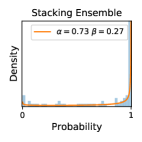

5.1 Distribution of Uncertainty Scores

Distribution of Uncertainty Scores Across Different Severity Levels As explained in Section 3, each uncertainty metric essentially defines an order/ranking among the data points. We conducted an analysis to better understand what data will be assigned high uncertainty under a particular uncertainty metric . Picking out the highest ranked data points (), we calculated the ratio of data points from each SL. Figure 4 summarizes the results as box plots for the Kaggle-DR and the Messidor-2 datasets; additional detailed statistics can be found in Table S.1 in the supplementary materials. From the plot and table, SL1 & SL2 examples account for a higher proportion among the top-ranked uncertain examples across the three ensemble methods. This finding matches our intuition that incipient disease examples (SL1 & SL2) are more likely to be considered uncertain by ensemble methods due to their ambiguity.

Comparing the three ensemble methods in Figure 4, the stacking ensemble method has the highest ratios of SL1 & SL2 data among the high-uncertainty examples it identified under both mean and var. TTA showed slightly better performance than MC-dropout but still falls behind the stacking ensemble method. Considering the fact that SL0 examples accounted for the majority of the dataset, the stacking ensemble method was much more precise (specific) in selecting truly ambiguous data points that were difficult to classify. From Figure 3, we can also see that the stacking ensemble method greatly outperformed the other two methods in finding false negatives under both mean and var uncertainty metrics.

In contrast, the MC-dropout method showed the worst overall performance among the three, as it can be seen from the high ratios of SL0 examples among the uncertain negatives in Figure 4. The histograms in Figure 2 provides another perspective to look into the phenomenon, where a decent proportion of MC-dropout model’s predictions on SL0 inputs entailed low confidence (far from 0 or 1), which from another angle explained why MC-dropout was less specific in terms of lower FNP; many no-DR inputs (i.e. SL0) were erroneously assigned high uncertainty by MC-dropout models.

It is still an open question why the evaluated MC-dropout networks signaled relatively high uncertainty on SL0 & SL3 & SL4 data that are less likely to be ambiguous. We conjecture that much of the “uncertainty” indicated by disagreement among test-time dropout samples actually reflects the stochastic nature of dropout networks rather than the real decision uncertainty associated with the data. It is worth noting that the MC-dropout model we evaluated was not weak per se; they all achieved above Area Under Curve (AUC) scores on test sets. The weakness of individual test-time samples (which explains their low-confidence predictions on SL0 & SL3 & SL4) might have been hidden when they are aggregated into an ensemble—a well-known advantage of ensemble learning. Our results suggested that the uncertainty information given by implicit ensemble methods such as MC-dropout and TTA might not be as reliable as that from explicit ensemble approaches (e.g., stacking ensembles). Similar findings on MC-dropout can be found in some previous papers [1].